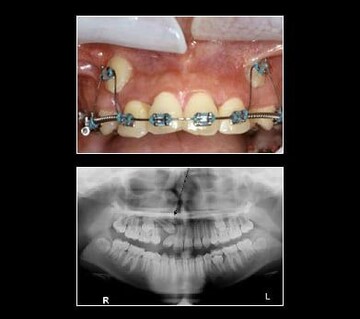

Ectopic canines are generally found in the Buccal Vestibule. Impacted canines may be retrieved with braces, using a surgical approach via a gold chain or straight wire. Tissue covering the tooth is uncovered. A chain or wire is attached to the tooth crown. Tissue is placed back over the tooth leaving the chain or wire coming out of the gum. For the purpose of this illustration a gold chain is used to retrieve the canines. The chain is attached to the tooth crown and the link is attached to a flexible archwire so that the wire is active (bent). Once a month, the wire is reactivated by using the next link up on the chain until the impacted canine erupts enough to attach a regular bracket on the canine. With the regular bracket in place, a more flexible wire is added directly to the bracketed canine. This process will bring the canine into position within the arch by forcing the canine to conform to the straight archwire form. This is a long process taking anywhere from 8-12 months.